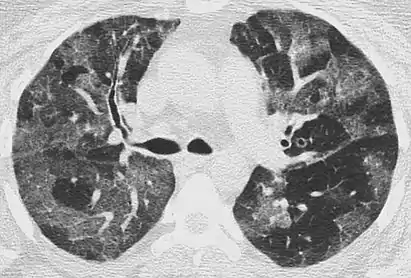

CT showing diffuse ground-glass opacities in periphery of both lungs in patient with COVID-19.

Ground-glass opacity is among the most common imaging findings in patients with confirmed COVID-19.[16][17] One systematic review found that among patients with COVID-19 and abnormal lung findings on CT, greater than 80% had GGOs, with greater than 50% having mixed GGOs and consolidation.[16] GGOs with mixed consolidation has most often been found in elderly populations.[18] Several studies have described a pattern among initial, intermediate, and hospital discharge imaging findings in the disease course of COVID-19. Most commonly, initial CT imaging reveals bilateral GGOs at the periphery of the lungs. During initial stages, this is most often found in the lower lobes, although involvement of the upper lobes and right middle lobe has also been reported early in the disease course.[16][18] This is in contrast to the two similar coronaviruses, SARS and MERS, which more commonly involve only one lung on initial imaging.[19][20] As the COVID-19 infection progresses, GGOs typically become more diffuse and often progress to consolidation.[11][18] This is sometimes accompanied by the development of a crazy paving pattern and interlobular septal thickening.[18] In many cases the most severe pulmonary CT abnormalities occurred within 2 weeks after symptoms began.[17] At this point, many individuals begin showing resolution of consolidation and GGOs as symptoms improve. However, some patients have worsening symptoms and imaging findings, with further increase in septal thickening, GGOs, and consolidation. These patients may develop lung "white-out" with progression to acute respiratory distress syndrome (ARDS) requiring treatment escalation.[17][21]

Preliminary reports have shown many patients have residual GGOs at time of discharge from the hospital. Due to the novelty of COVID-19, large studies investigating the long-term pulmonary CT changes have yet to be completed. However, long-term pulmonary changes have been seen in patients after recovery from SARS and MERS, suggesting the possibility of similar long-term complications in patients who have recovered from acute COVID-19 infection.[22]